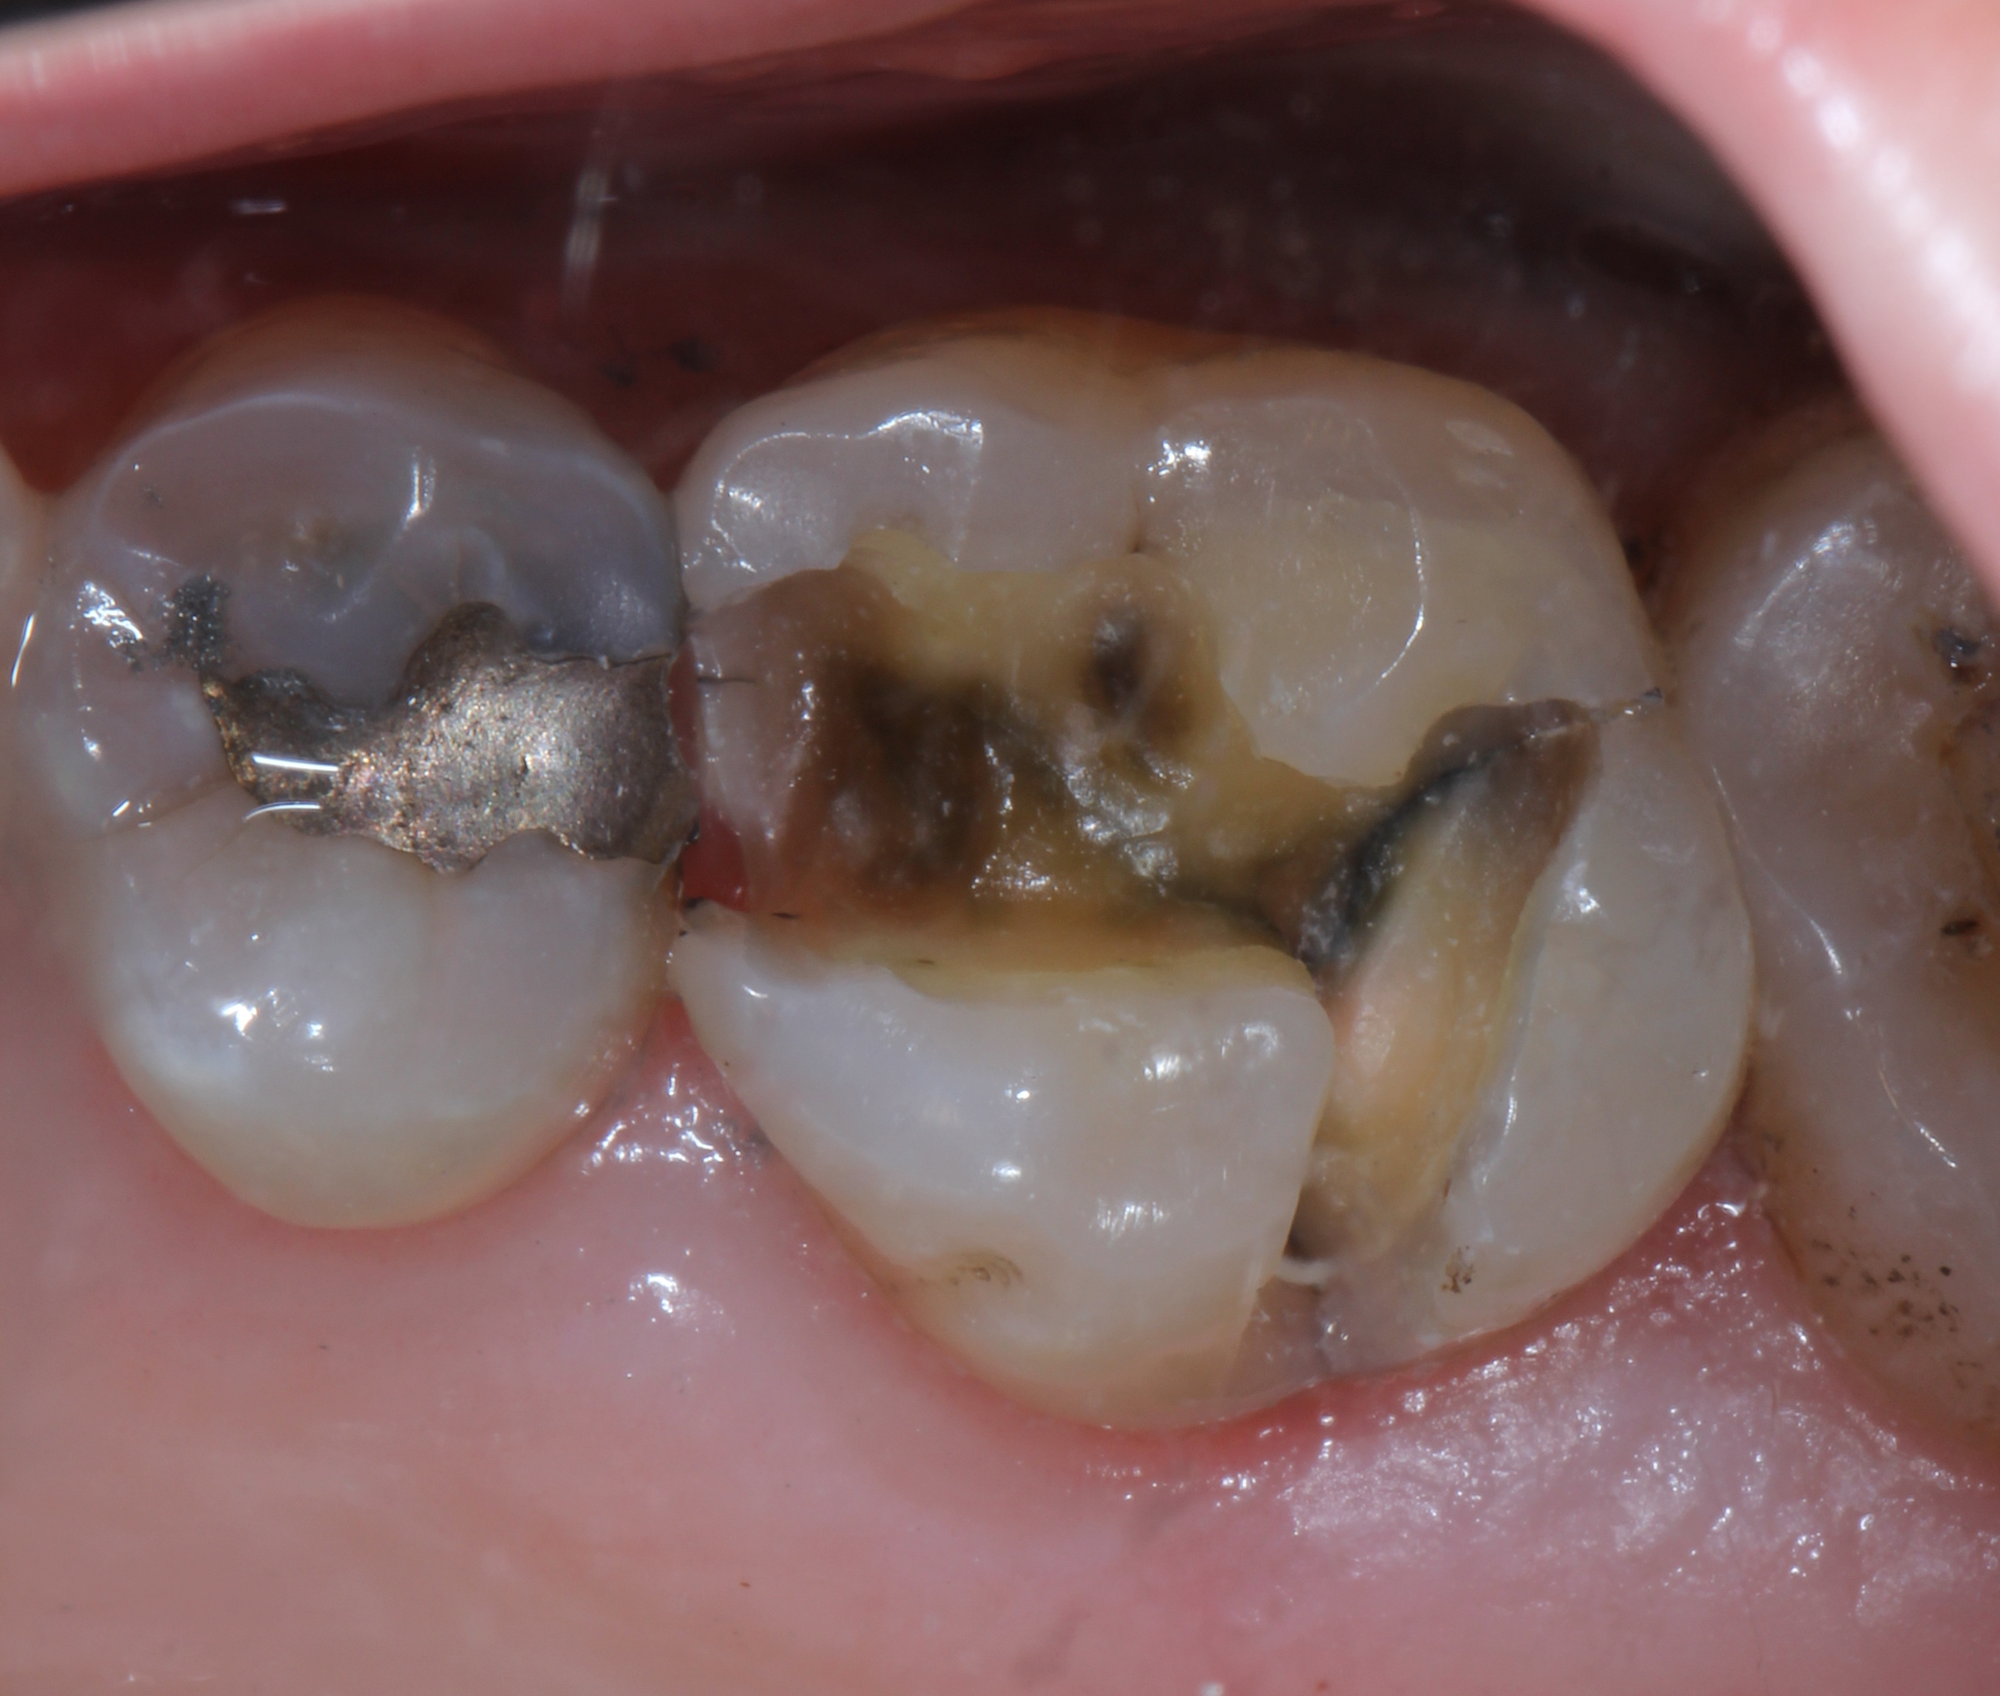

Fig. 6

We scanned the margins of the maxillary first molar with The Canary System and found Canary Numbers ranging from 47 to 76 around the margins of the amalgam (Fig. 5). Removal of the amalgam restoration confirmed the presence of caries in both areas (Fig. 6).

Using The Canary System we were able to diagnose the source of the pain-secondary caries around the margin of an amalgam restoration. Accurate detection allowed us to correctly identify the pain source, treat the caries and preserve tooth structure. Caries detection is more than simply shining laser light on teeth and looking at the glow. It involves understanding how energy interacts with tooth structure and restorative materials. Using the PTR-LUM technology in The Canary System, one can accurately examine the margins of restoration to detect caries and cracks.